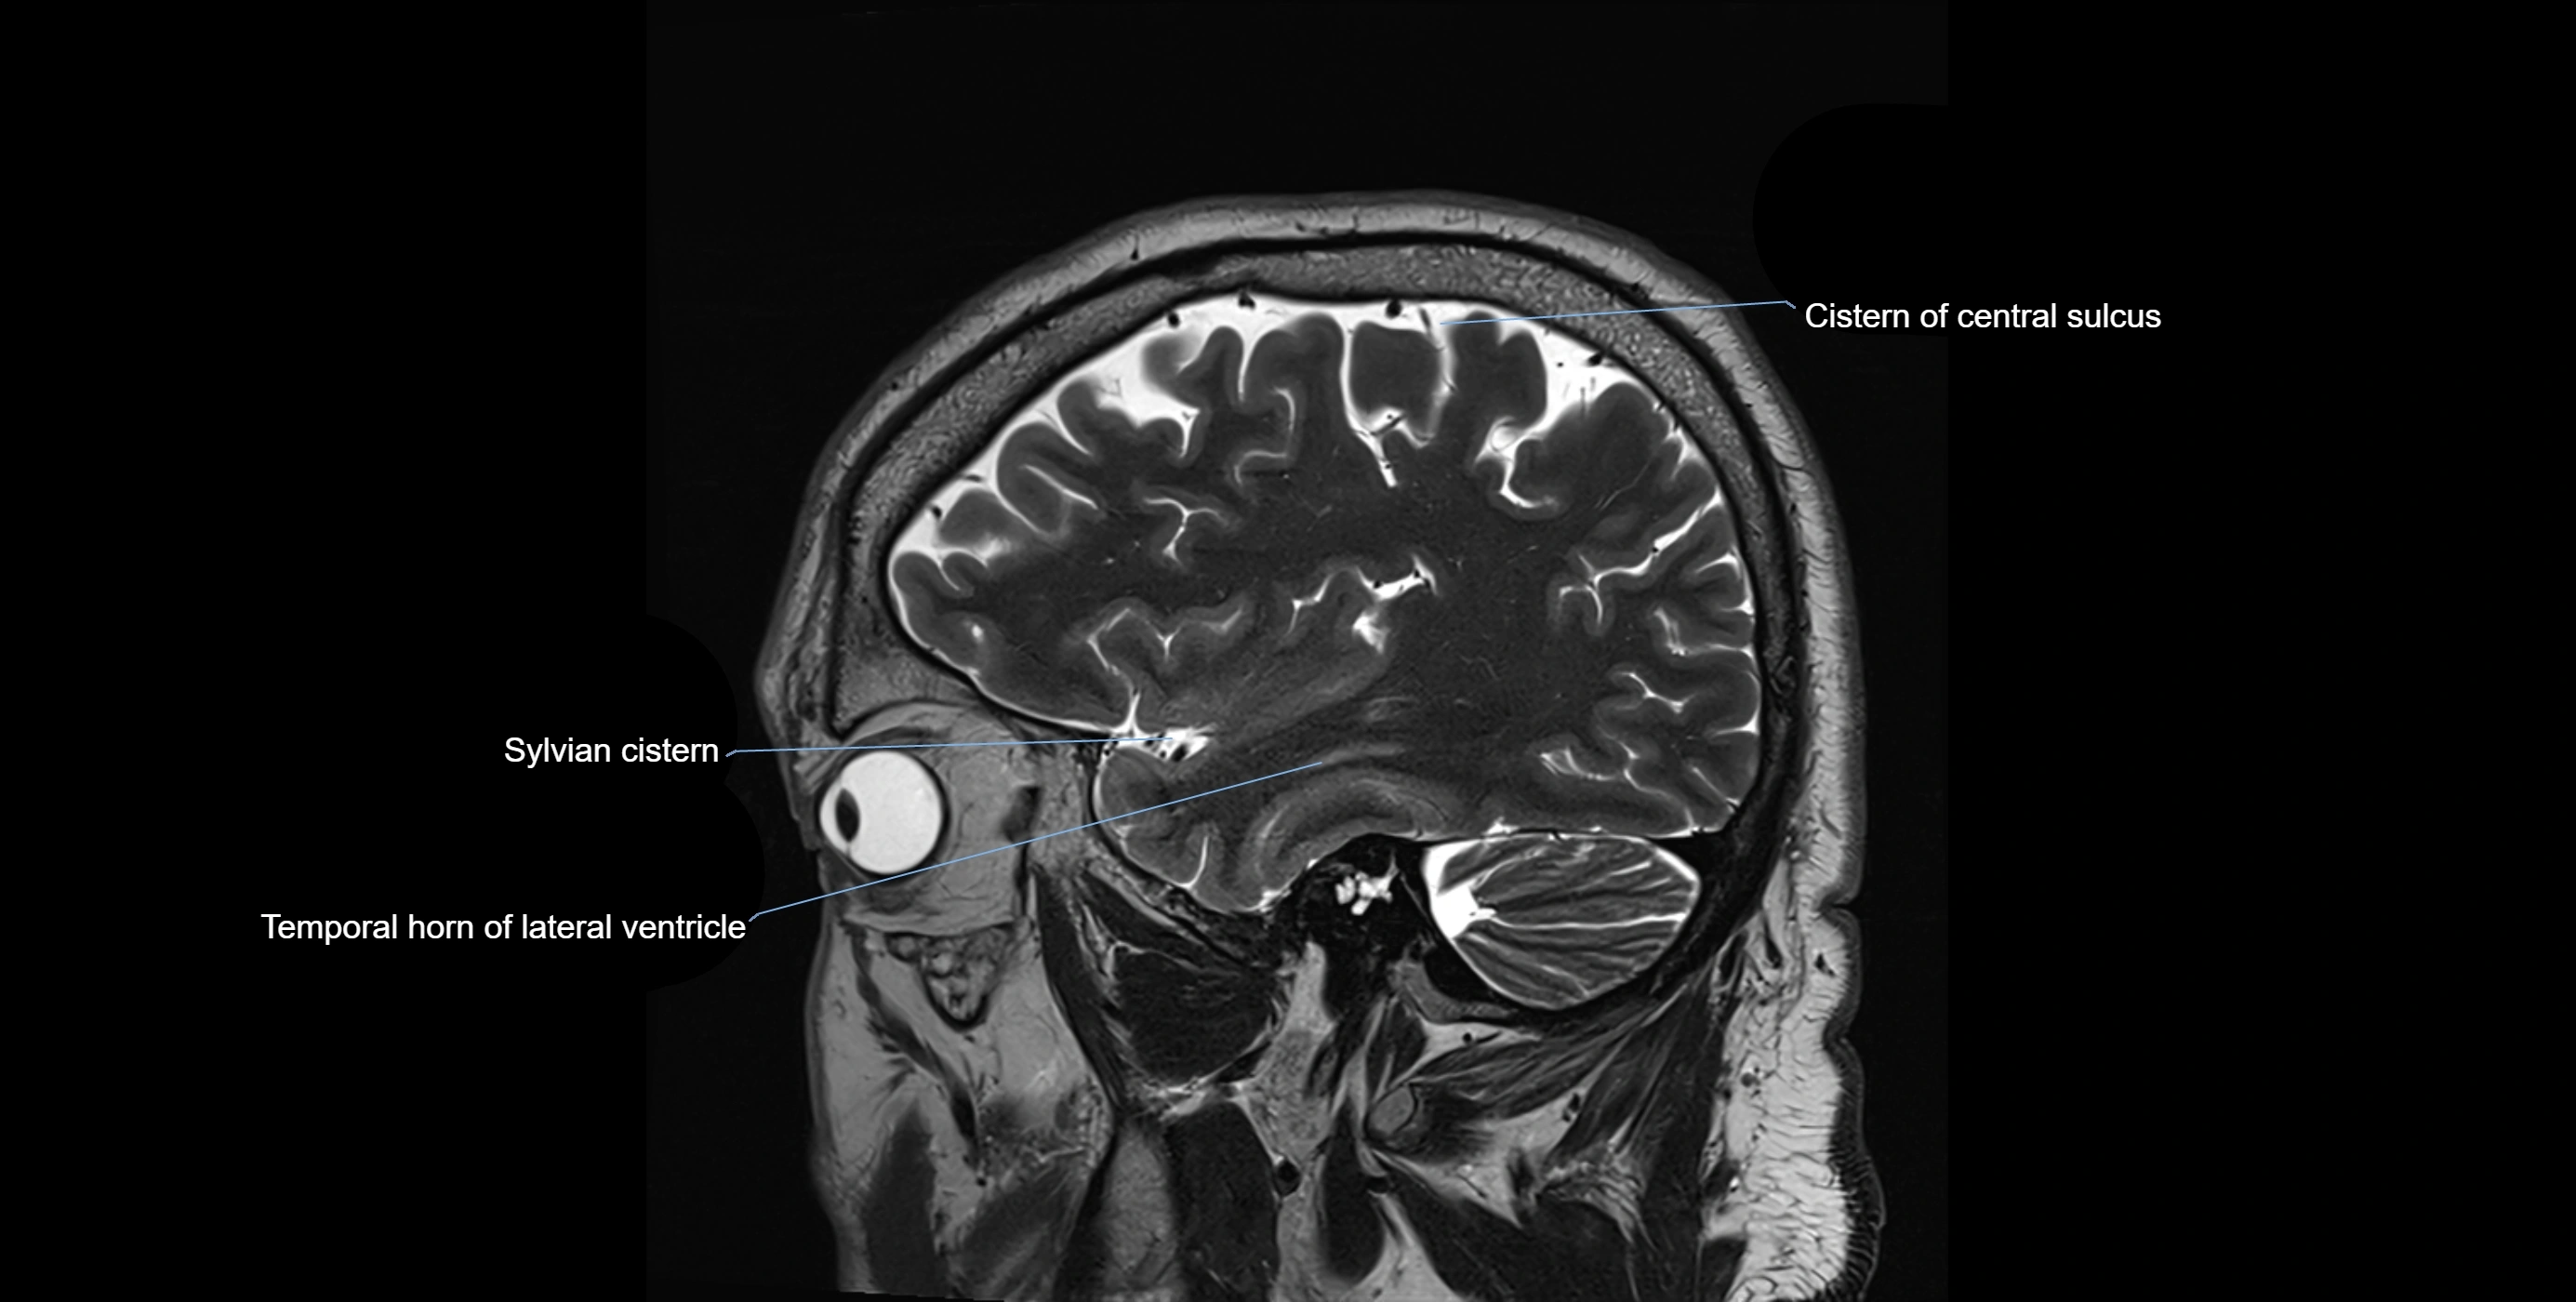

MRI images

image